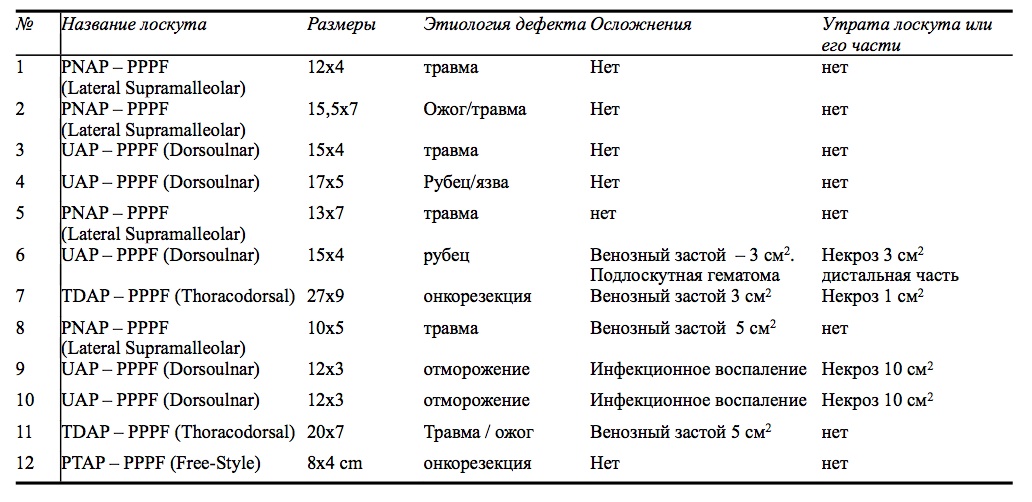

По сравнению с техникой пересадки лоскутов на питающей ножке, которая включает мышцу. Техника пересадки лоскутов, питающая ножка которых включает мышцу при малых и среднего размеров дефектах выполнима в один этап. Причем, формирование самого лоскута возможно на одной с дефектом конечности, что освобождает пациента от вынужденного положения, длительного стационарного наблюдения, осложнений со стороны опорного аппарата. Поэтому в конце прошлого века пластика лоскутами на мышечной ножке стала более приоритетной, чем кросс-пластика. Однако накопленный опыт применения такого вида операций показал, что техника не является полностью безупречной. К недостаткам относят видимые изменения контуров тела после операции, известным как феномен «bulky flap» или «толстого лоскута» (Рис. 10 А,Б), требущего проведение хирургической коррекции по эстетическим показаниям – дебалкинг [15]. Кроме этого, при заборе вместе с кожей значительного объема мышечной ткани, имеет место и деформация контуров тела в донорской области (Рис. 10 В), которая проявляется видимым дефицитом объема.

Рис. 10. А,Б – Цифровое фото нижних конечностей, где произведено закрытие раневых дефектов кожно-мышечными лоскутами. Определяется выраженная избыточность мягких тканей и нарушение контура голени после пластики кожно-мышечным лоскутом (bulky flap). В – Цифровое фото правой голени (вид сзади) определяется деформация контура голени в области взятия кожно-мышечного лоскута